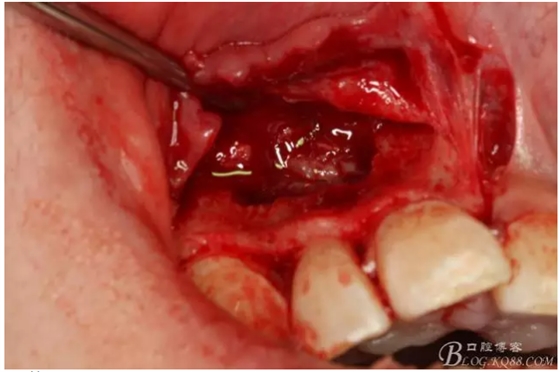

圖3.依缺損部位為中心,逐漸去骨,完整暴露出囊壁。

圖4.摘除囊壁后形成的巨大骨腔